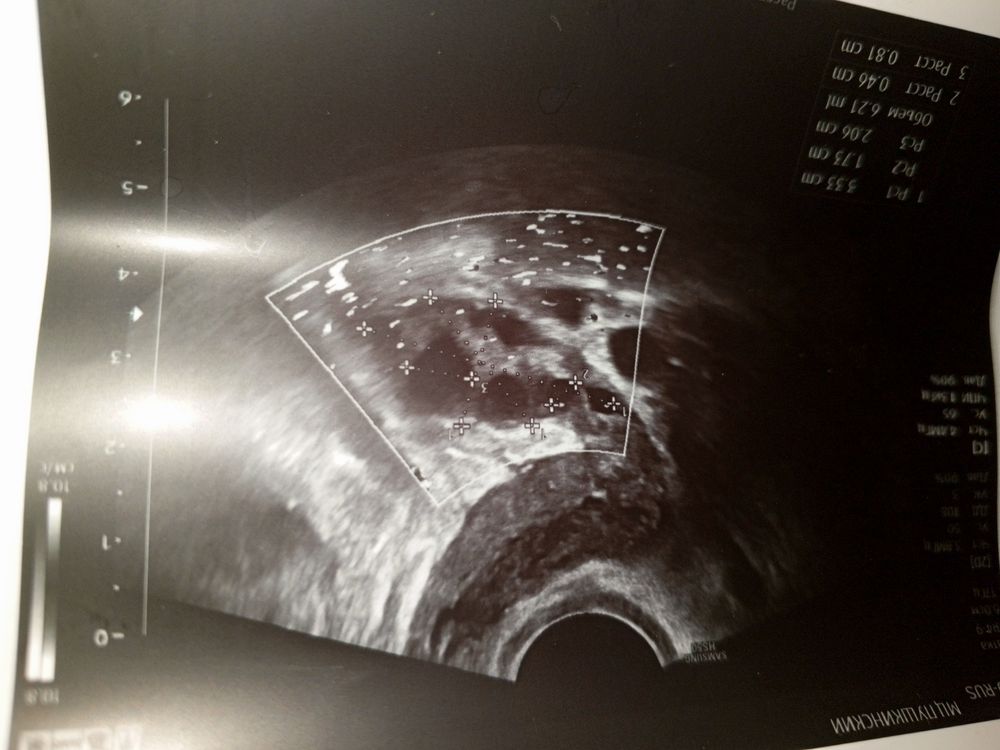

УЗИНу подскажите, на фото же только фолликулы, нет жёлтого тела?

Может ли врач не увидеть овуляцию?

Может ли не быть житкости?

Фолликулы в яйчнике если не росли могут ли они в течение цикла куда-то деваться?Просто замечала у себя что на 4 день было 8 фолликул диаметром 5-8мм и на 13 день таким же диаметром но только фолликул уже 6, вот и интересно это была овуляция или куда они делаются?